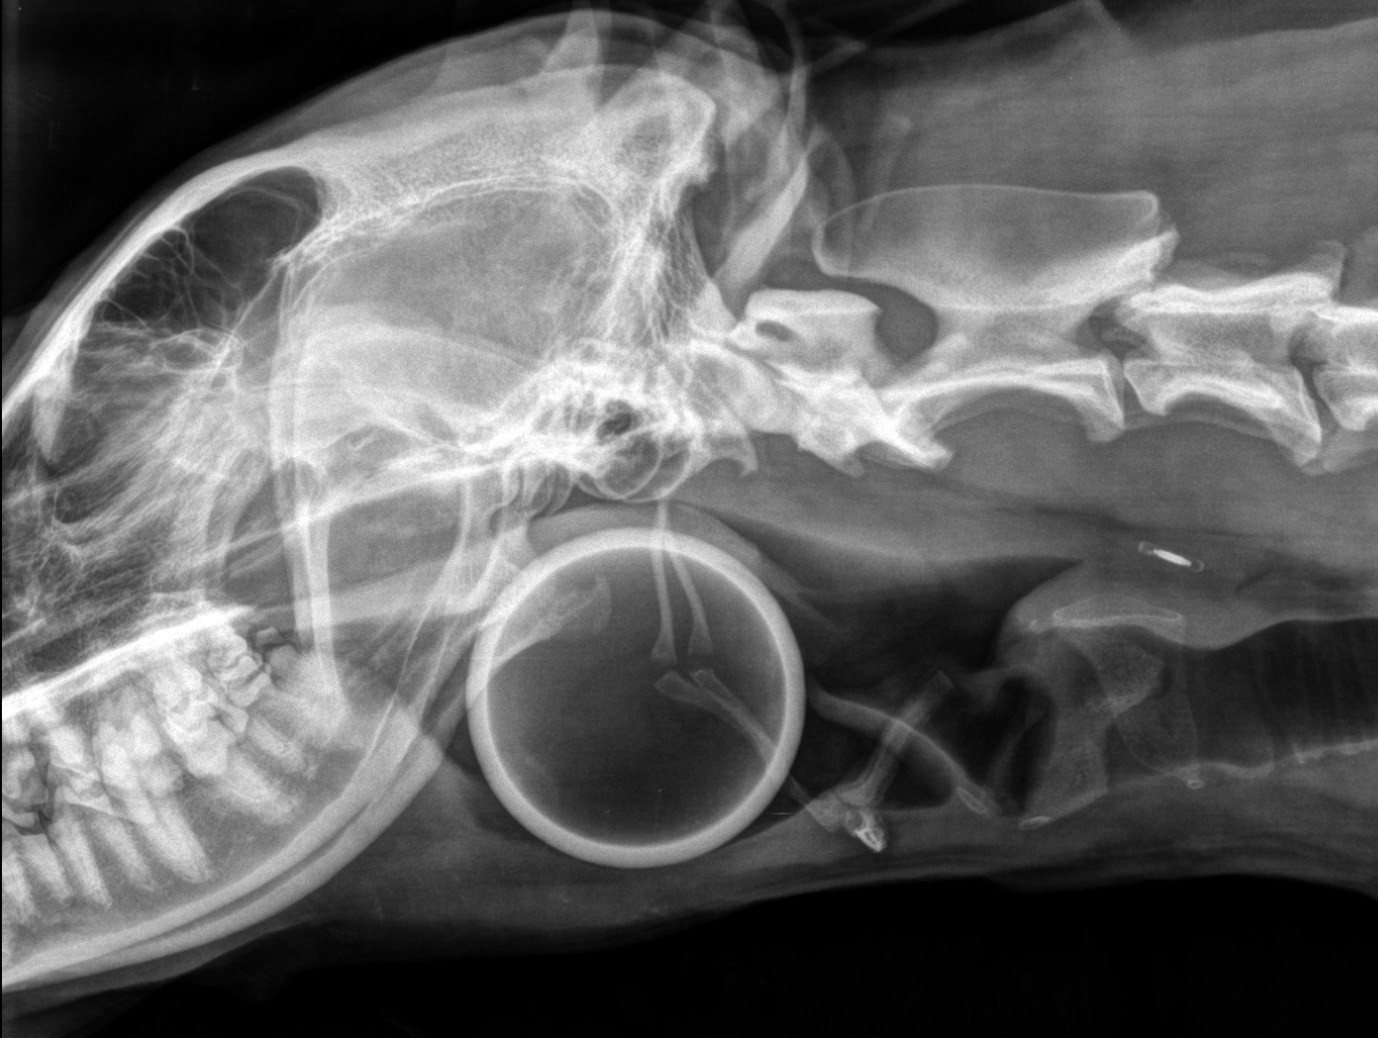

Cas de corps étranger pharyngé chez un berger allemand

Une chienne berger allemand âgée de 3 ans est référée à V24 suite à un iléus gastro-intestinal. Elle présente du ptyalisme et des vomissements depuis 4 jours. L’examen clinique : montre un ptyalisme intense, une gène à la déglutition, une dilatation abdominale modérée avec tympanisme gastrique et des bruits inspiratoires augmentés de type cornage associés…